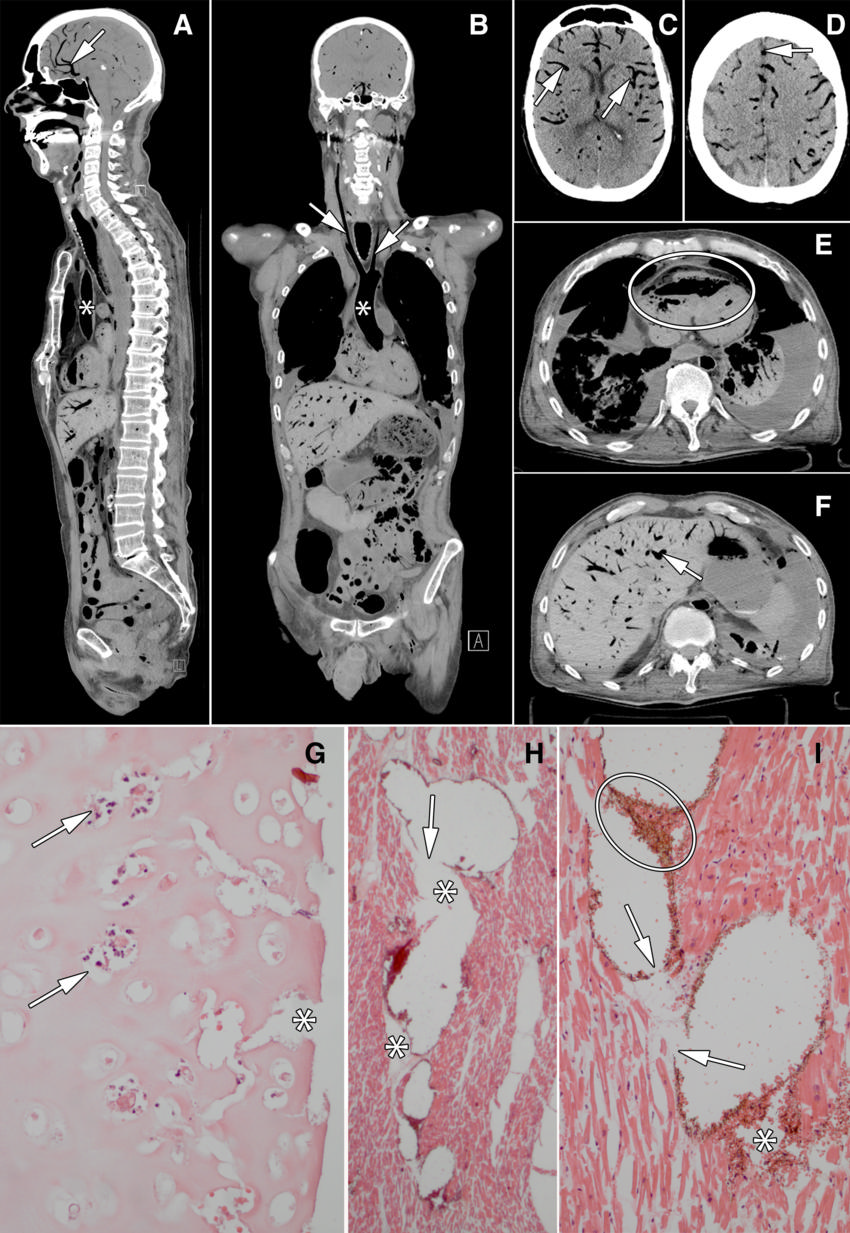

Figure 2. Images in 60-year old man who underwent bilateral lung transplant 2 months before death. He developed postoperative delirium and was treated for pneumonia. Just prior to death he developed hypotension and agonal breathing. There were signs of elevated jugular venous pressure. Resuscitation during asystole was unsuccessful. Patient died under clinical suspicion of central pulmonary embolus or cardiac tamponade. Conventional autopsy identified a possible myocardial infarction and thrombo-emboli as cause of death, whereas cause of death at minimally invasive autopsy was massive air embolus. The reference standard committee concluded that minimally invasive autopsy correctly identified the cause of death. Images show aorta (∗ in A and B), carotid arteries (arrows in B), visceral blood vessels (cerebral blood vessels: arrows in A, C, D; liver blood vessel: arrow in F), and right ventricle (oval in E). G, Photomicrograph of luminal side of trachea shows disappearance of mucosa and submucosa; tracheal cartilage is necrotic with empty lacunae, nuclear debris (arrows), and clefts (∗). H, I, Photomicrographs of myocardium show blood vessels inflated by air that pushes erythrocytes to the walls and causes rupture of vessels (arrows), allowing air (∗) and erythrocytes (oval in I) to escape into interstitial space, thereby tearing the tissue.